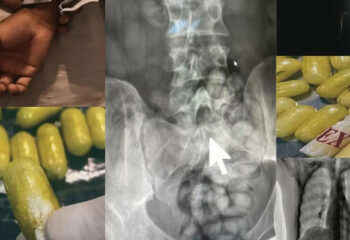

ശരീരത്തിനുള്ളിൽ ലഹരിമരുന്ന് ഒളിപ്പിച്ച യാത്രക്കാരൻ ഖത്തറില്‍ പിടിയിൽ

ദോഹ: ഖത്തറിൽ ശരീരത്തിനുള്ളിൽ ലഹരിമരുന്ന് ഒളിപ്പിച്ച യാത്രക്കാരൻ പിടിയിൽ. ഹമദ് അന്താരാഷ്ട്ര വിമാനത്താവളത്തിൽ […]